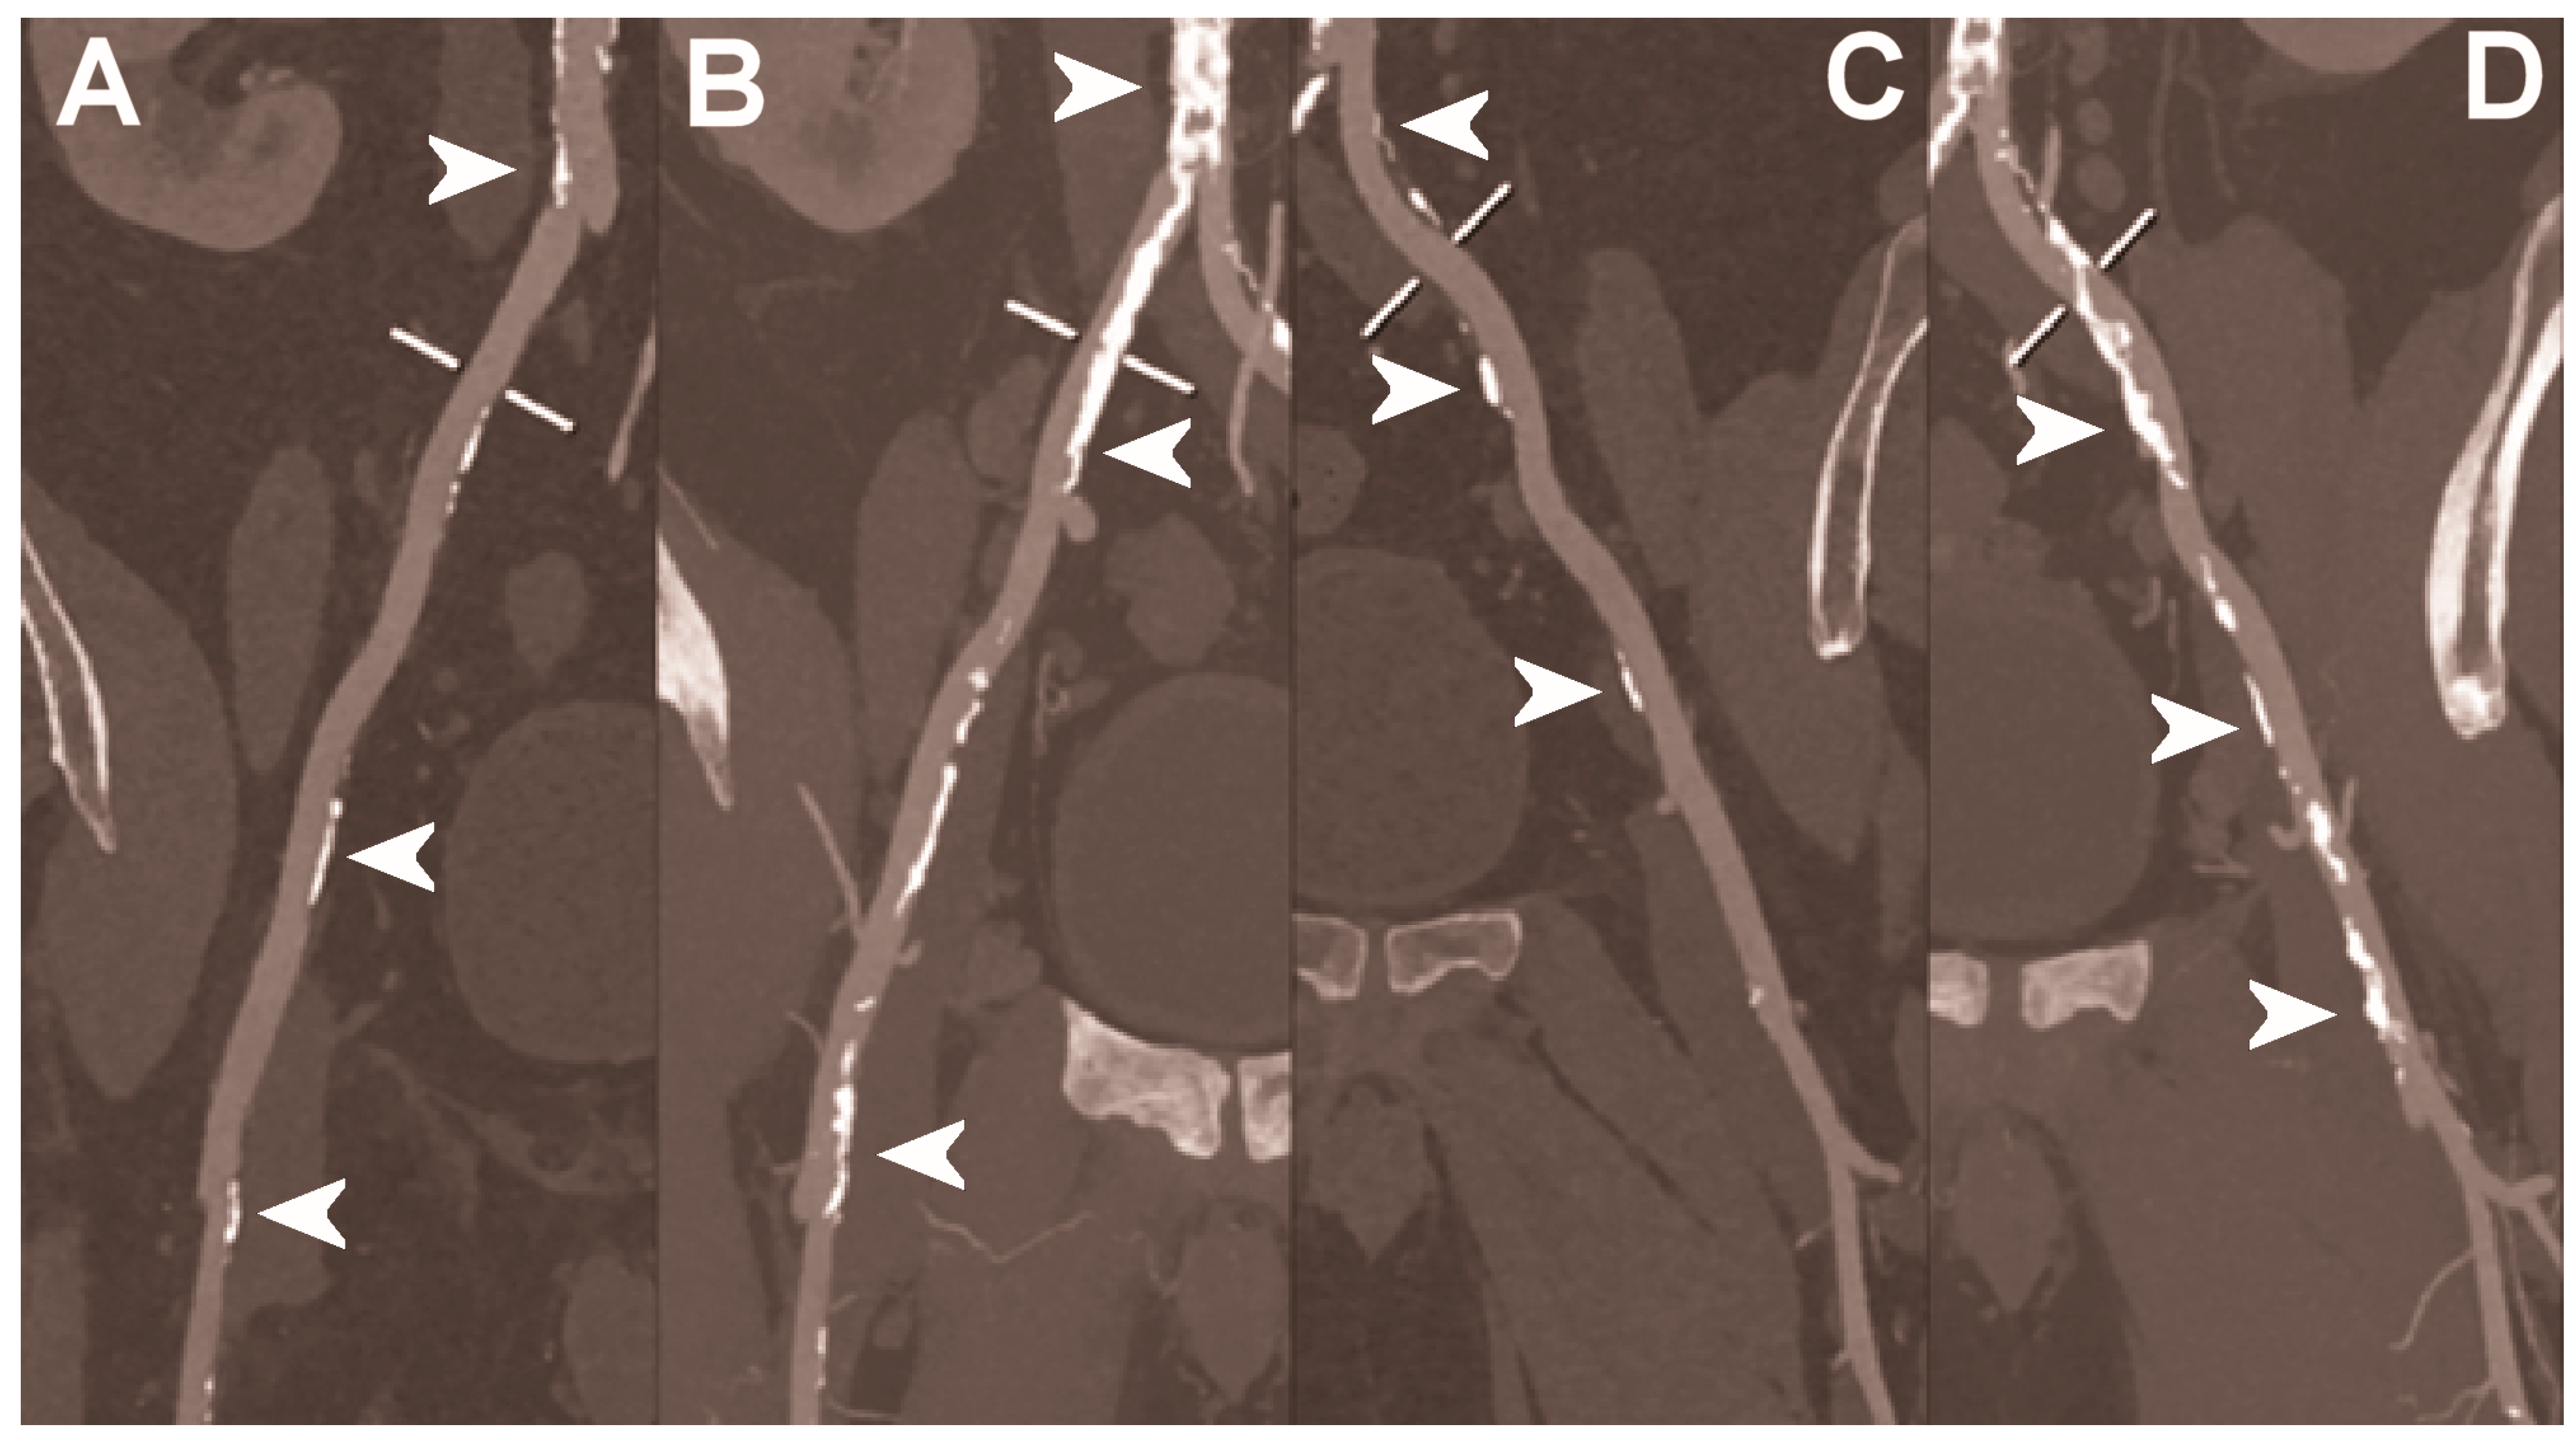

Figure 6.

Abdominal CT angiography using photon-counting computed tomography. The figure shows advanced multiplanar reconstructions without and with MIP algorithm of a distal abdominal aorta and ilio-femoral arterial axes derived from a photon-counting CT (Scanner: NAEOTOM Alpha, Siemens) acquisition (A,B right; C,D left). The projection start in the abdominal aorta carrefour and end in the right/left common femoral artery. There are massive calcifications along the common iliac arteries; however, both MPRs (A,C) and MIPs (B,D) are so sharply defining the edges of the structures that lumen assessment is not compromised (arrowheads).

Figure 7.

Abdominal CT angiography using photon-counting computed tomography. The figure shows advanced multiplanar reconstructions of an abdominal aorta and ilio-femoral arterial axes derived from a photon-counting CT (Scanner: NAEOTOM Alpha, Siemens) acquisition (A,B). In (A) the projection starts in the abdominal aorta at the level of thoraco-abdominal junction and ends in the right common femoral artery while in (B) it ends in the left common femoral artery. While there are significant calcifications along the vessels (arrowheads in A and B), the vessel wall is so sharp that the fact that there is no lumen reduction appears to be quite natural as compared to the common blooming effect seen with conventional energy-integrating detectors.